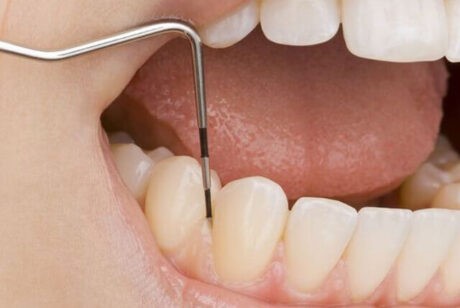

歯周病の進行度を把握するためにプラークの付着量、歯周ポケットの深さ、出血の有無、歯の動揺度などを検査します。

※歯周病の進行度合いによって少し痛みを伴うことがあります。